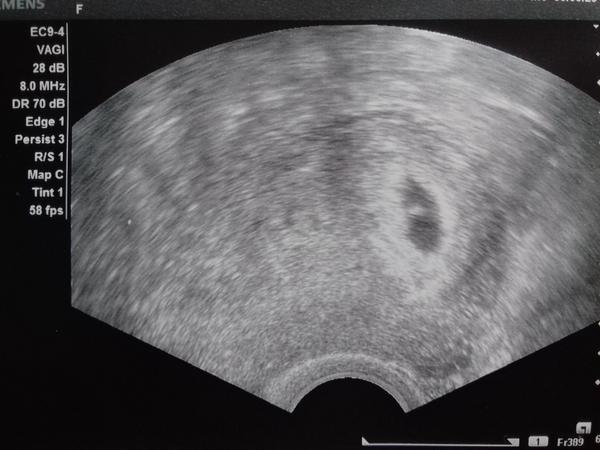

Děkuji všem za uklidňující odpovědi 🙂 Akorát teď jsem ještě ve větším stresu..Přišla jsem od doktorky a na ultrazvuku vůbec nic neviděla 😲 Tak mi vzaly krev a ve čtvrtek jdu znova..Musím počítat s variantou, že to může být mimoděložní😢😢😢 Příznaky těhotenské mám jasné, testy zřetelně pozitivní, týden se už v noci potím úplně do mokra a bolesti břicha a zad..☹ Doufám, že ten prdík malý není prostě ještě vidět a že se ukáže 😢

Tak to vypadá na dobré cestě😍 Ve čtvrtek mi braly znovu hcg po dvou dnech stouplo z 600 na 1200 🙂 Proto na ultrazvuku nešlo nic vidět, doktorka říkala, že se většinou ukáže od 1500..Takže v pondělí mě čeká další ultrazvuk a věřím, že drobečka už uvidím❤ Takže opravdu posunutá ovu 🙂

Ahooj holky, pardon že píšu, až tak pozdě 🙂 V pondělí jsem byla na ultrazvuku a bylo to tam 😍😍😍 Podle doktora jsem 5tt a v pondělí jdu opět na další, jestli už půjde vidět srdíčko 🙂 Strašně se mi ulevilo a věřím, že vše bude dobrý!❤ Hlavně prcek dává každý večer o sobě vědět, mám hrozný nevolnosti 😀 A chci se zeptat, říkaly jste si o fotky, hned takhle na začátku? Strašně bych chtěla fotečku, toho malého zárodečku tam 🙂 Ale nevím jestli to není blbý říct si .. 🙂